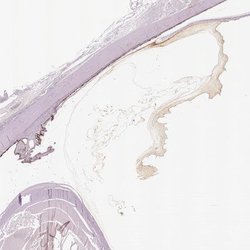

ABIN4341481 IHC

Other validation